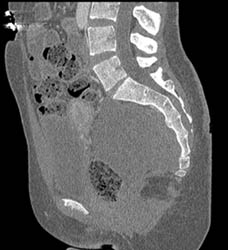

Gout